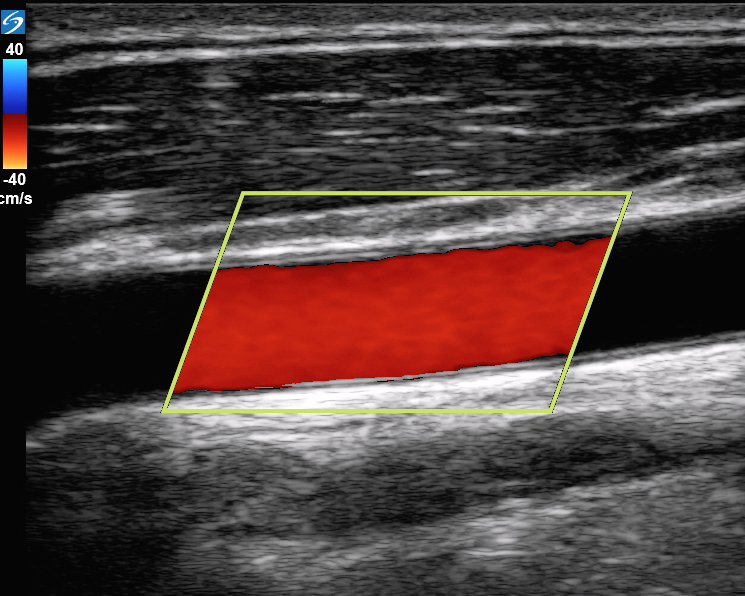

カラーフローを伴う頚動脈の画像